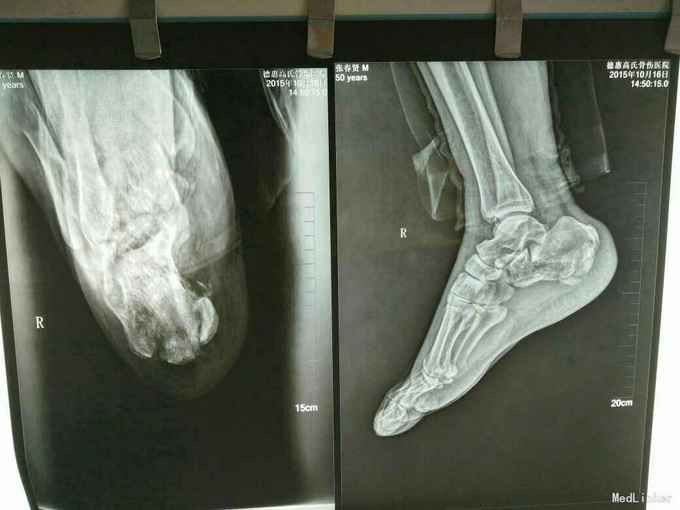

双足跟骨骨折

摔伤致双足跟部疼痛.肿胀.活动受限1小时

双足跟处肿胀,畸形明显,可触及骨擦感及异常活动,

双足跟骨骨折,手术治疗,